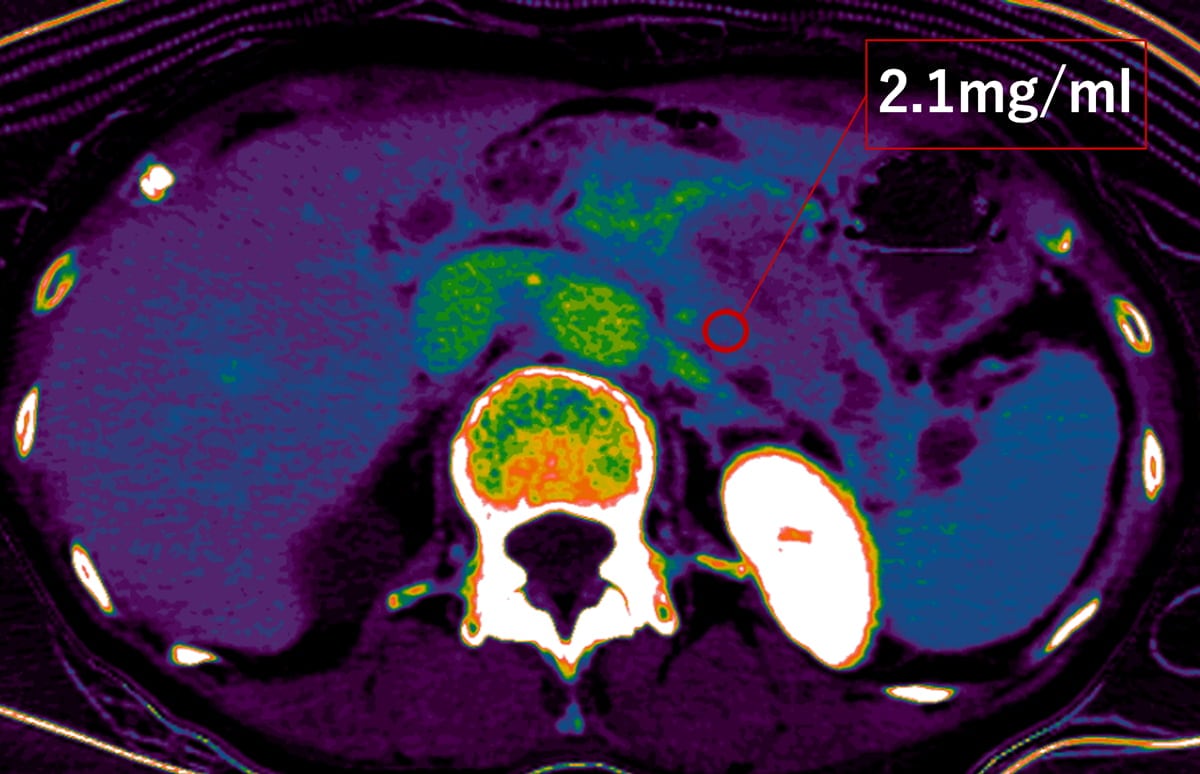

最近では、低電圧CTやdual energy CT (DECT)を用いることで、造影剤の使用量を減らしつつ、低keV画像でより造影パターンを明瞭化することで腫瘍の検出率を向上させられるようになっている。抗癌剤のデリバリー効率は線維性間質量(desmoplastic反応)に影響されることから、細胞外容積分画(extracellular volume fraction:ECV) を測定することで化学療法による治療効果を予測することが可能であると報告されている(Fujitaら。EJR2023: 162)。Single energy CT (SECT)では造影前後のCT値からECVを算出していたが、DECTでは平衡相のヨード密度だけでミスレジストレーションの影響がないECV値を定量化できるとされる。

今回の症例における腫瘍のDECT-ECV値は32%程度であった。明確な基準はないが、ある文献ではDECT-ECV値が26%以下で化学療法に感受性であるとしており、今回の症例は化学療法に抵抗性であることが予測される。

本検査は食道静脈瘤が認められたことから、肝臓プロトコルによる撮像を行っている。膵臓をターゲットとするのであれば、動脈相よりタイミングをもう少し遅らせた膵実質相を撮像するべきである。また、ECVを評価する際は、十分造影剤が間質に到達した時相が好ましく、本検査で施行した180秒後の平衡相の撮像は、早すぎると予想される。